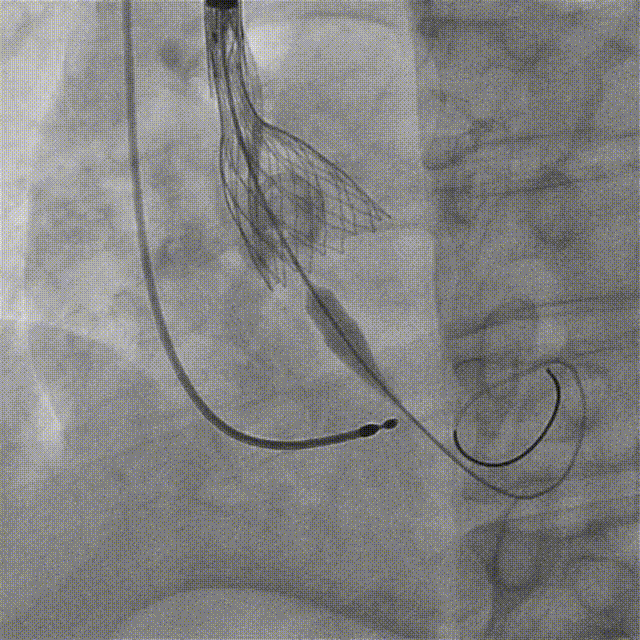

工作位造影,左右重合位下,无窦侧瓣下2mm,小弯侧半个菱形格,瓣膜形态好、同轴性佳

多角度评估,左冠切线位下,瓣膜形态呈类直角梯形,结合术前CT,无窦侧钙化为主,水平夹角不大,小弯侧深度可接受,脱钩趋势保持不变或小弯侧→大弯侧轻微,遂决定完全释放

瓣膜稳定脱钩释放

根部造影,瓣膜形态良好,位置理想,小弯轻微瓣周漏(预估左右融合嵴处);猪尾导管测压无压差